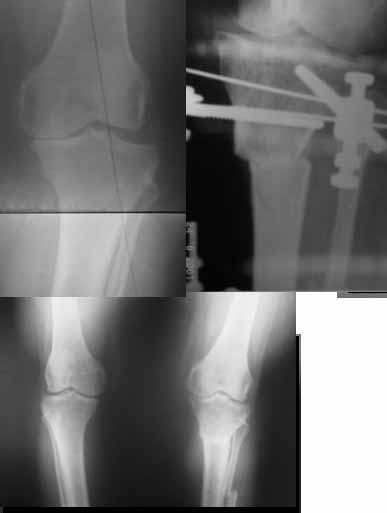

Yesterday one leg was done (my plan to make both in one session were cancelled because of external reasons). So much exciting and useful experience.

The osteotomy line i planned to make a bit oblique, but not so as you suggested. But at the moment of osteoclasis after corticotomy through the anterior stab wound the line became almost as you described. Now problem is how to reproduce thee line at the next leg ;-)

The prominent fragment seems to be useful for cosmetic purposes, because aesthetic guys perform medialization of the distal fragment to gain attractive curve at the medial side of the leg. Also all locking options became available - initially i planned to engage only two most

proximal 45 degree holes.

I cut the fibula because i externally rotated the distal fragment by 6-7 degrees. With only angular correction it didn't show any displacement.

Today CT for estimation of rotation was performed, results i will see only tomorrow. Rotation of the operated limb can be corrected with the second surgery. Comments/critics are welcome.

Снимки в приложении - фас сравнительный с неоперированной ногой. Жду критики.

Впрос про остеотомию большеберцовой непраздный. Эта получилась при надломе несколько более наклонно, чем я делал (сейчас проблема,

как на второй ноге сделать так же). Вот этот высоящий "зуб" центрального отломка не заменит ли в плане косметики то, что получается при медиализации дистального?